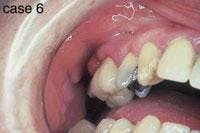

CASE 6

Peripheral giant cell granuloma (PGCG)

1. What causes a PGCG?

a. irritation

b. injury

c. both a & b

d. none of the above

2. Where is the PGCG likely to occur?

a. hard palate

b. gingiva

c. floor of mouth

d. any of the above

3. What is the preferred treatment for the PGCG?

a. surgical excision

b. removal of irritation sources (calculus)

c. no treatment necessary

d. both a & b